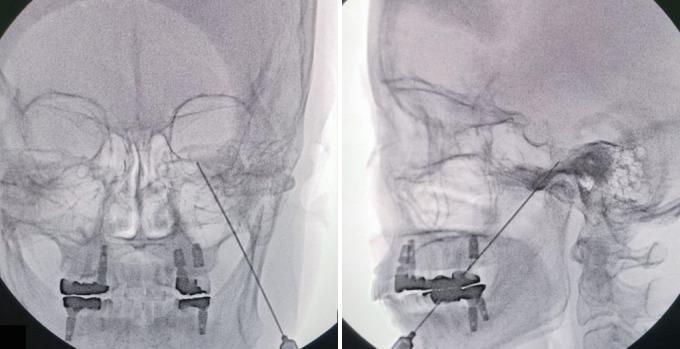

Percutaneous Procedures for Trigeminal Neuralgia.

Microvascular decompression is the gold standard for the treatment of trigeminal neuralgia (TN). However, percutaneous techniques still play a role in treating patients with TN and offer several important advantages and efficiency in obtaining immediate pain relief, which is also durable in a less invasive and safe manner. Patients' preference for a less invasive method can influence the procedure they will undergo. Neurovascular conflict is not always a prerequisite for patients with TN. In addition, recurrence and failure of the previous procedure can influence the decision to follow the treatment. Therefore, indications for percutaneous procedures for TN persist when patients experience idiopathic and episodic sharp shooting pain. In this review, we provide an overview of percutaneous procedures for TN and its outcome and complication.

微血管减压术是治疗三叉神经痛(TN)的金标准。然而,经皮技术在治疗TN患者中仍发挥着作用,并且在获得即时疼痛缓解方面具有几个重要优势和效率,而且以微创和安全的方式实现的疼痛缓解也是持久的。患者对微创方法的偏好会影响他们将接受的手术。神经血管冲突并非TN患者的必要条件。此外,先前手术的复发和失败会影响后续治疗的决策。因此,当患者出现特发性发作性剧痛时,TN经皮手术的适应证仍然存在。在本综述中,我们概述了TN的经皮手术及其结果和并发症。